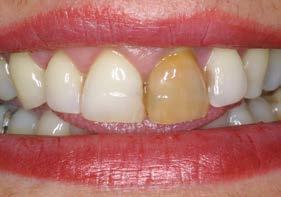

Figuras 1 y 2. Imágenes iniciales de la paciente. Se observa el diente en posición 21 con un cambio de color evidente y supuración espontánea a través del surco gingival. Asimismo, se aprecia el impacto estético del cambio cromático en la sonrisa y en el aspecto del frente anterosuperior.

Se presenta el caso de una paciente femenina de 47 años de edad al inicio del tratamiento, quien acude a consulta por dolor y supuración en el incisivo central superior izquierdo. En las imágenes iniciales se observa un diente con un cambio de color llamativo y una supuración espontánea a través del surco gingival (Figura 1). Esta alteración cromática, además de reflejar un problema asociado al diente, afecta de manera significativa la estética del frente anterior, como se aprecia en la imagen de sonrisa (Figura 2).

Estos hallazgos confirman el éxito del procedimiento quirúrgico y de la posterior carga progresiva, con un mantenimiento óptimo de los tejidos duros y blandos a lo largo de más de dos décadas (Figura 15). Los cambios entre el momento inicial y el final del tratamiento son evidentes, especialmente al comparar la imagen intraoral de la primera visita con la tomada a los 22 años, donde la mucosa que rodea al diente 21 —y posteriormente al implante— se muestra engrosada, en buen estado de salud y con una estética destacable. Asimismo, la comparación entre la radiografía inicial, que evidenciaba el fracaso del tratamiento de conductos del diente en posición 21, y la radiografía a los 22 años, que muestra el implante sin pérdidas óseas asociadas, resulta elocuente (Figuras 16 a 19).